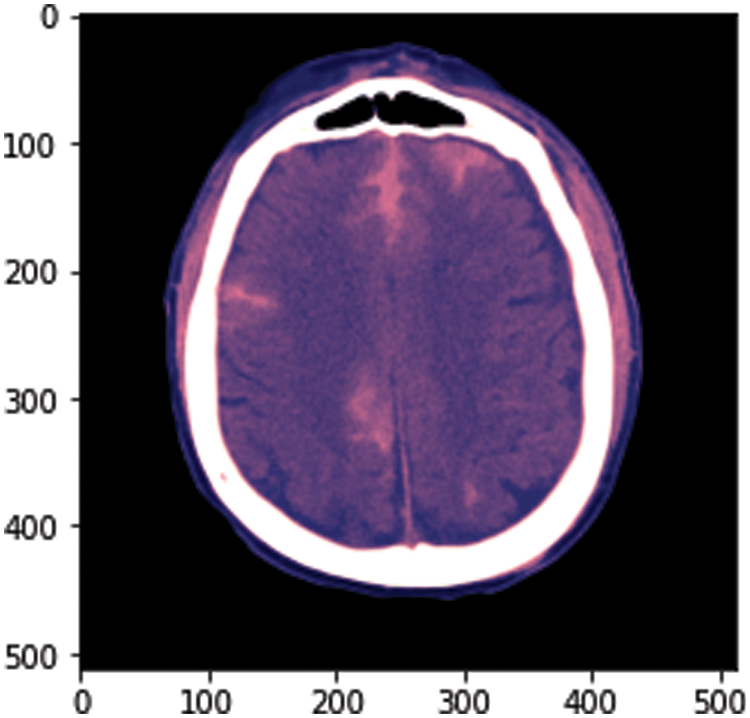

3.5 Image Processing for Segmentation Volume Calculation

To calculate the volume estimation, the physionet dataset is used for experiments, which has approximately 33 CT Scan slices per patient. Slice thickness is 0.5 cm or 5 mm. The idea behind this is to calculate the total volume of hemorrhage. For this, we took data from one patient from a dataset consisting of 33 CT scan image slices and separated hemorrhage slices from the rest of the slices. The hemorrhage image is of black and white pixels and we need to be careful while performing calculations. The white area represents the hemorrhage region as shown in Fig. 4. After this, we have designed our algorithm to calculate the volume that is discussed in Fig. 5.

Figure 5: Sample image from the dataset

At the start of this approach, we convert .dcm image to .png. The dataset RSNA has DICOM format images, which have metadata of images. There is an uneven distribution of data in the dataset. The major portion of the dataset includes the data of patients without hemorrhage. We have converted one image from .dcm to .png to show the sample image from our dataset and after converting, we got the result shown in Fig. 5.